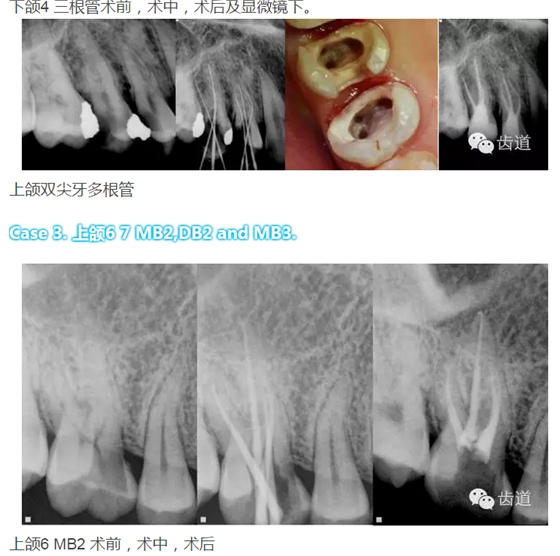

下頜第一前磨牙:多為單根管,少數(shù)為雙根管,三根管發(fā)生率為 0.46-0.5%,側(cè)支根管發(fā)生率44.3%;

下頜第一磨牙:為3-4個根管,遠(yuǎn)中雙根管的發(fā)生率為51.4% 左右,側(cè)支根管發(fā)生率為30%左右;